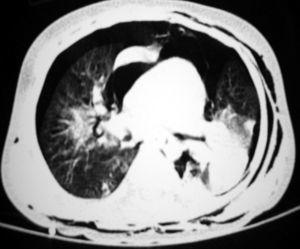

Presentamos el caso de un lactante de 15 meses sin antecedentes de interés, que presentó un cuadro de insuficiencia respiratoria aguda y progresiva tras la aspiración de un producto químico compuesto por hidrocarburos alifáticos de cadena larga. La radiografía de tórax mostraba un infiltrado alveolointersticial bilateral. Se decidió su ingreso y tratamiento con oxígeno, antibióticos y corticoides. En las siguientes 4 h desarrolló un enfisema subcutáneo cervical. La TC de tórax evidenció una consolidación alveolar en ambas bases, neumotórax bilateral, neumomediastino y enfisema subcutáneo (fig. 1). Ante el rápido deterioro clínico del paciente se decidió su traslado a nuestro centro. Aunque a su llegada presentaba una dificultad respiratoria moderada y mantenía una oxigenación normal con oxígeno a través de mascarilla facial, presentó un deterioro clínico e hipoxemia progresivos, por lo que se evacuó el neumotórax derecho y se inició ventilación no invasiva en modo CPAP, sin mejoría evidente (saturación de Hb entre 88 y 92 % a pesar de 10 cmH2O en CPAP y fracción inspiratoria de oxígeno de 0,9). Se decidió entonces la intubación endotraqueal y ventilación mecánica convencional en modo SIMV-P (PIP 35 cmH2O, PEEP 9 cmH2O, FiO2 0,80). El índice de oxigenación calculado una hora después era de 28, observándose en la radiografía de tórax signos de síndrome de distrés respiratorio agudo, por lo que se decidió aplicar la VAFO con los siguientes parámetros iniciales: Paw: 30 cmH2O, ΔP: 92 cmH2O, frecuencia: 11 Hz y FiO2: 0,70. Doce horas después, ante la imposibilidad de disminuir de forma significativa los parámetros ventilatorios, se decidió administrar surfactante pulmonar. Unas 12 h más tarde comenzó a objetivarse una mejoría de la oxigenación (fig. 2) que permitió iniciar el descenso progresivo de los parámetros ventilatorios. El niño se mantuvo con VAFO durante 10 días y se extubó tras 24 h de transición ventilación convencional, sin otras incidencias.

Figura 1.TC pulmonar. Consolidación en ambas bases pulmonares, neumotórax bilateral y neumomediastino.